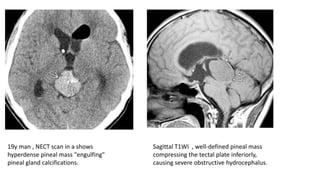

19y man , NECT scan in a shows

hyperdense pineal mass "engulfing"

pineal gland calcifications.

Sagittal T1WI , well-defined pineal mass

compressing the tectal plate inferiorly,

causing severe obstructive hydrocephalus.